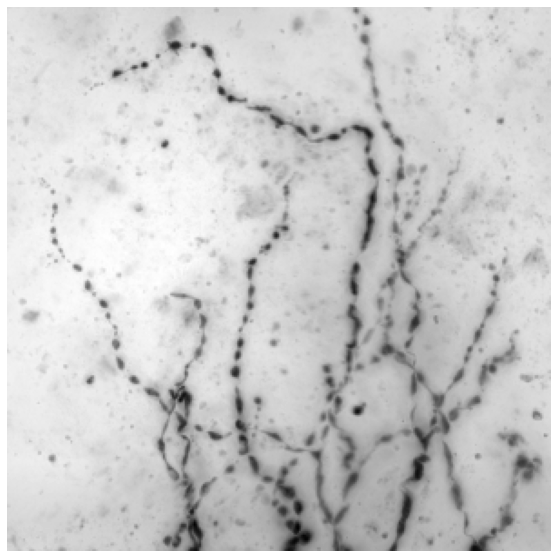

We tested our approach on three data sets. The Brain comprises 14 light microscopy scans of mouse brain, sized . We use 10 of them for training and 4 as a validation test. Neurons contains 13 light microscopy scans of mouse neurons, sized . We use 10 for training and 3 for validation. MRA is a publicly available set of Magnetic Resonance Angiography brain scans [3]. We crop them to size by removing their empty margins, and use 31 annotated scans for training and 11 for validation. A sample image from each data set can be found in Fig. 4.

| Brain | Neurons | Neurons | MRA | |

|---|---|---|---|---|

| Input | ![]() |

![]() |